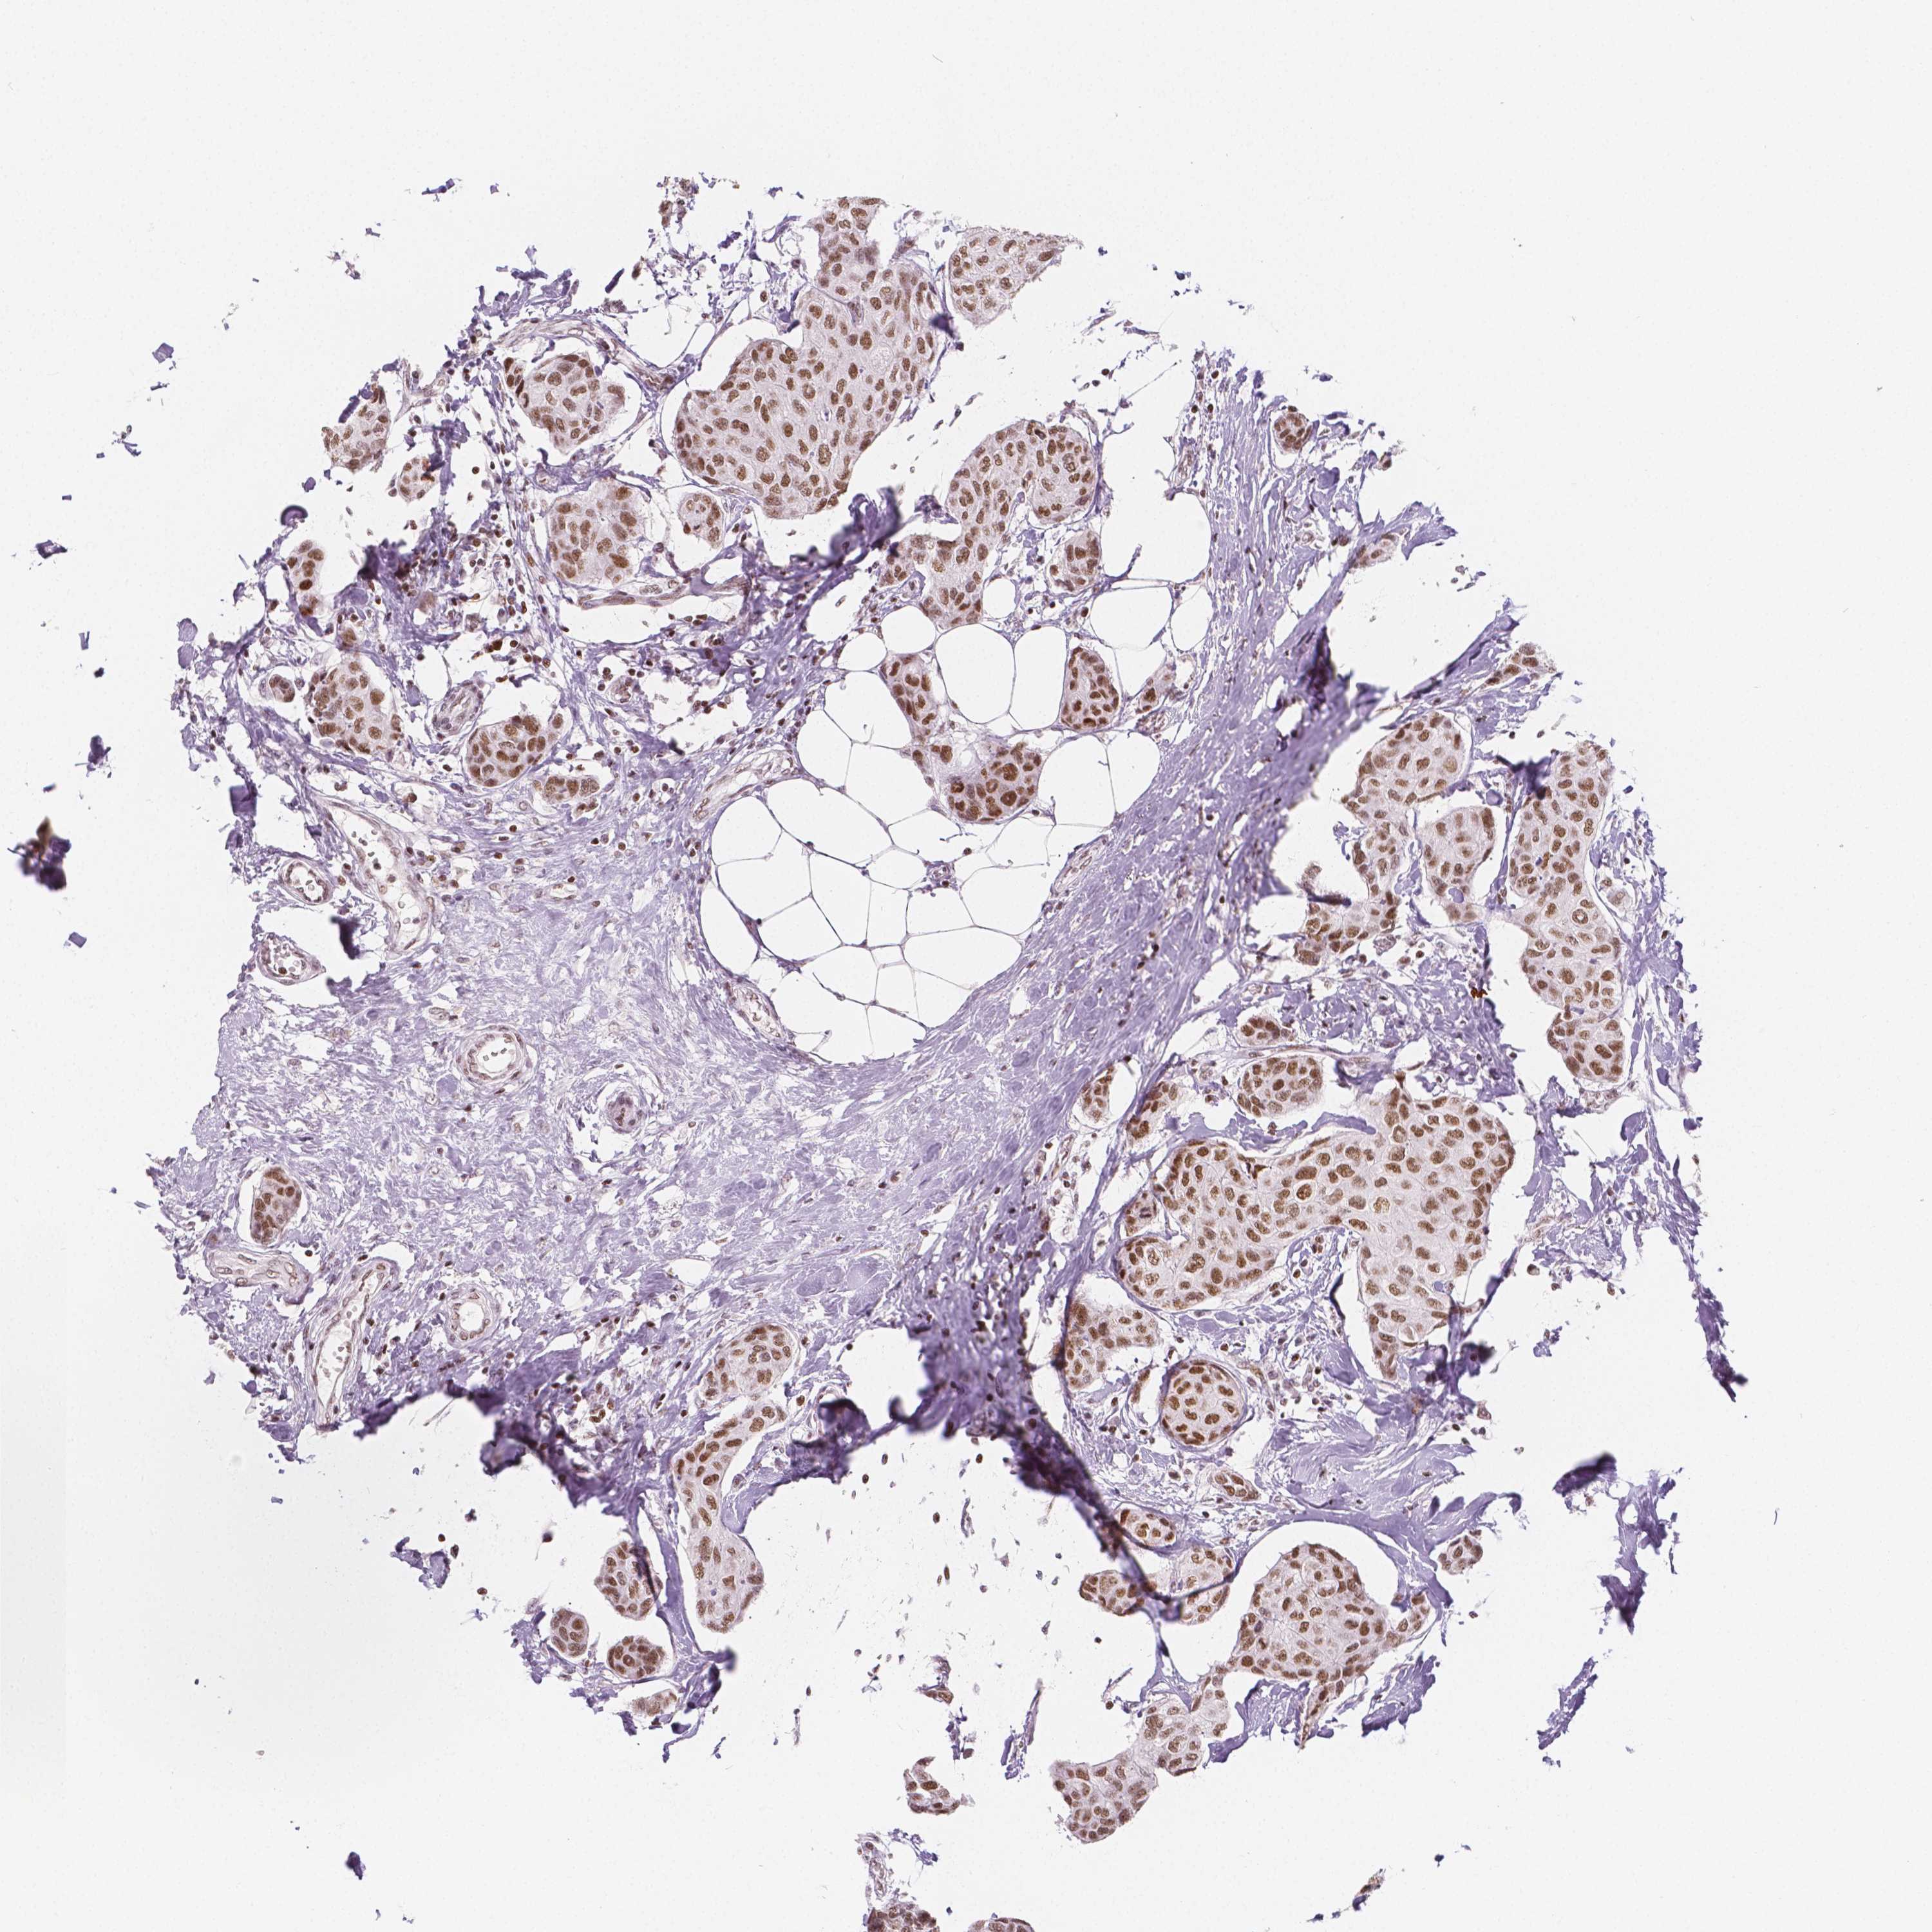

HDAC1

BRCA TCGA BRCA VALIDATION PROTEIN EXPRESSION